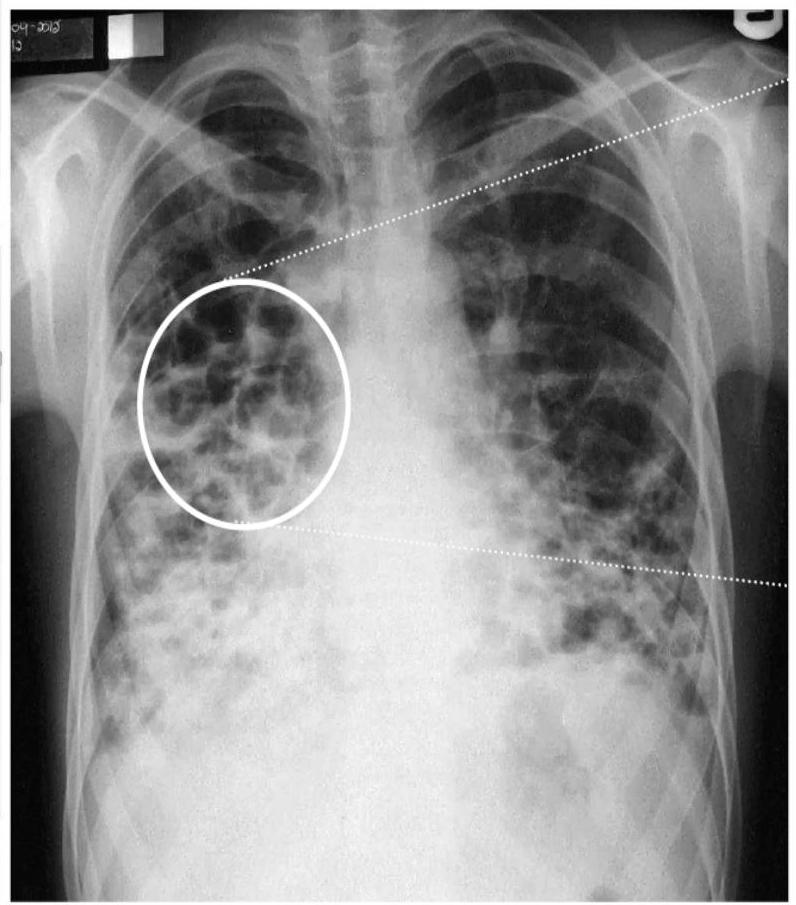

- ☐ Chest X-ray: increase in size and loss of bronchovascular markings, crowding of bronchi, and loss of lung volume. Severe case: Honeycombing.

Radiographic Findings (Chest X-ray)

Conglomerating cysts of varying size and wall thickness. “Honeycomb” sign.

Radiographic Findings (Signs)

Bronchial wall thickening and widening with parallel configuration. Tram track sign.